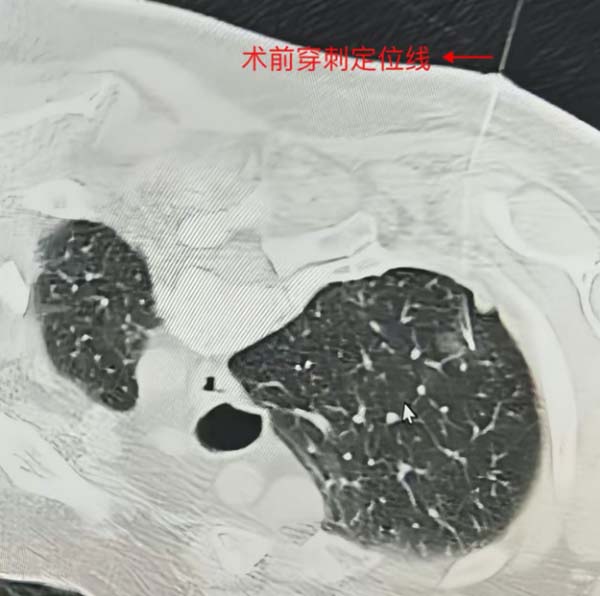

图2 术前穿刺定位线

在外院胸外科专家的悉心指导下,我院刘全新主任医师,丁仕琳主治医师与手术麻醉科、护理团队密切配合,顺利完成肺结节切除术,用时约90分钟,出血量不足20ml,术后患者生命体征平稳,最后病理结果回示:微浸润性腺癌。